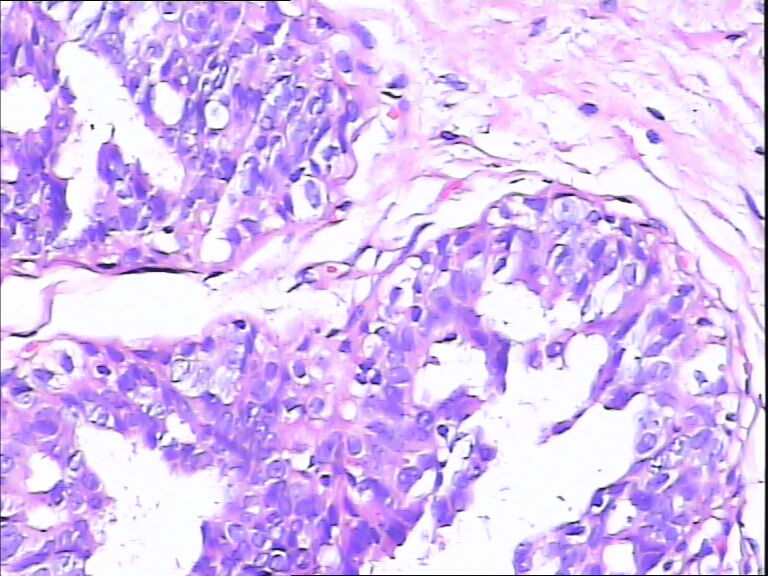

40岁,发现乳腺包快5月